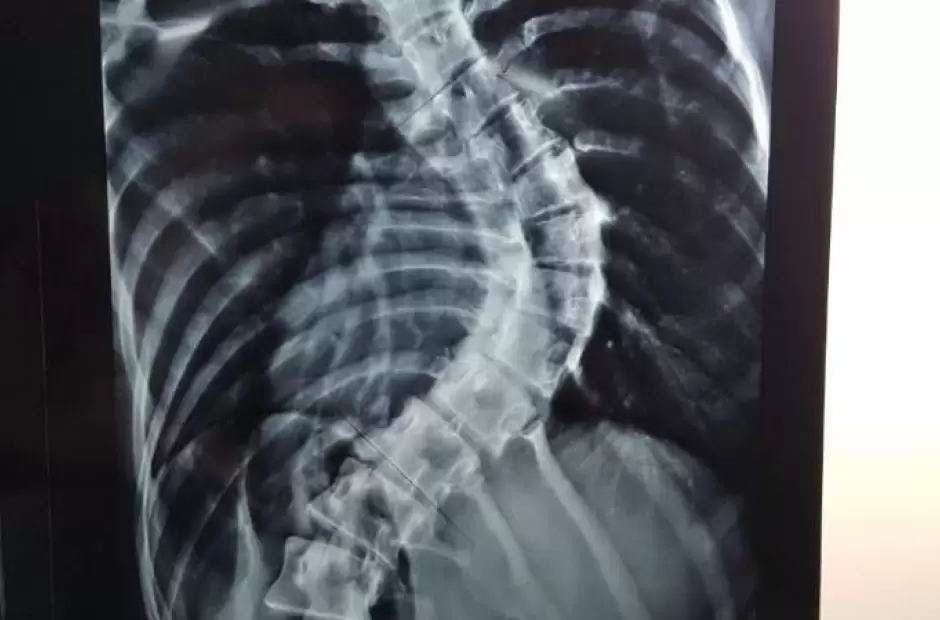

Exitosa cirugía de columna en el Hospital San Juan Bautista

Un equipo de cirujanos especialistas en columna vertebral del Hospital San Juan Bautista y del Hospital de Niños “Eva Perón”, realizó una intervención quirúrgica muy compleja y poco frecuente en pacientes de edad adulta.

Durante el procedimiento realizaron la reducción de la desviación y fijación sobre un 80 por ciento de la columna vertebral ?lumbar y dorsal. Tal como lo relatan los profesionales, esta clase de intervenciones se realizan, usualmente y a menor riesgo, en pacientes de edad temprana, antes que la malformación se agudice y los huesos ganen cierta rigidez. Sin embargo, en este caso, la paciente ya tenía 20 años de edad y una deformidad descompensada en su columna.

Nicolás Flores Kanter, médico que participó de la cirugía, explicó que “la intervención en sí misma llevó cinco horas en quirófano, fue compleja porque implicaba mucha pérdida de sangre; pero la paciente despertó bien y estuvo internada en sala durante 5 días, que era el objetivo del equipo de tratamiento. Ahora volvió para controles y se encuentra en perfectas condiciones, sin dolores, ni complicaciones, solo vino para que se le quitaran los puntos”.

El equipo de profesionales contó con Nicolás Flores Kanter, Traumatólogo especialista en columna del Hospital Interzonal San Juan Bautista; Pablo Ovejero Traumatólogo especialista en columna del Hospital de Niños Eva Perón y Ángel Sosa Anestesiólogo del Hospital Interzonal San Juan Bautista. También participaron los instrumentistas del Hospital San Juan Bautista, Florencia Cesarini y Claudio Álvarez.